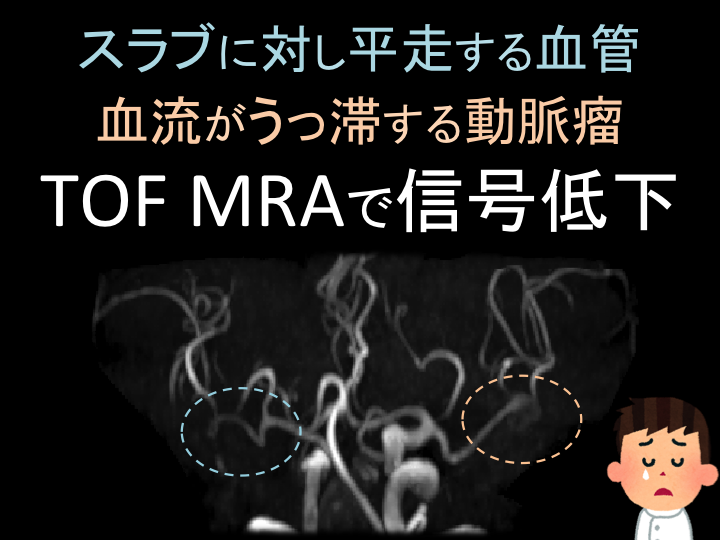

頭頸部のCT・MRI 第3版 | 尾尻博也, 酒井 修 |本 | 通販 | Amazon。Amazon.co.jp: RHOTON 頭蓋内脳神経解剖と手術アプローチ : 松島。頭部MRAのちょっとした工夫(1) | MRIfan.net。【大特価】サキホコレ 白米 4キロ 秋田県産 6年度産 米 お米 さきほこれ。ドクターインタビュー - 心臓血管外科医|高梨秀一郎先生。m3電子書籍 | 形成外科 2023年5月号【特集】乳輪乳頭の疾患。JBC Operators | Japanese Bifurcation Club 2022。1.5T ECHELON Vegaの使用経験 - 株式会社日立メディコ - inNavi。富山大学第1外科(Thoracic and Cardiovascular Surgery。バイオメカセラピー研究会(Shinichiro ISHII) | * 今日は。Dream HEART vol.303 慶應義塾大学医学部 小児科教授 高橋孝雄。初診時 造影 CT:腎動脈下に最大短径60mm の腹 部大動脈瘤を認め。筑波大学整形外科 - 同門の坂下孝太郎先生が 東日本整形外科学会。。